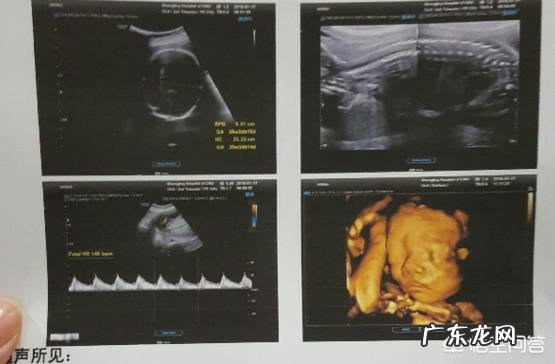

文章插图

常规基础检查、孕期保健(合并症排查、分娩方式)、尿常规、产科超声(胎儿生长发育测量)、产科超生单项、多普勒听胎心、胎心监护 。